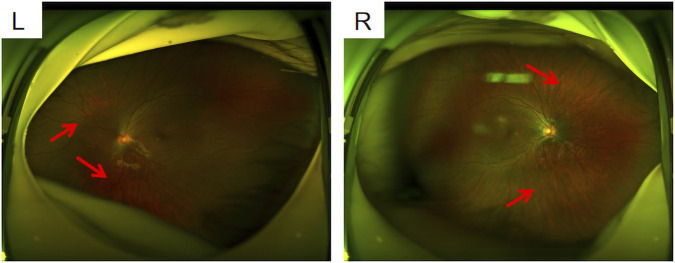

Methods: Comprehensive examinations, including ophthalmology, otology, and orthopedic evaluations, were performed to identify the disease phenotype of the proband. Furthermore, whole-exome sequencing (WES) and Sanger sequencing were performed to identify the molecular basis of the disease. In silico analysis and a minigene splicing assay were conducted to verify the pathogenicity of the splice site variant. The clinical phenotypes of the reported STL patients were then reviewed.

Results: The proband presented mild symptoms with early-onset high myopia and mild scoliosis. A novel de novo splicing variant (NM_080629.3: c.4069-1G>T), in the COL11A1 gene was identified in the proband via WES and confirmed via Sanger sequencing. Minigene splicing assays verified that this variant resulted in abnormal splicing of the COL11A1 transcripts because of the skipping of exon 54 and retention of 21 bp in intron 53. The literature review revealed that the most common phenotypes associated with STL type 2 include myopia and hearing impairment.